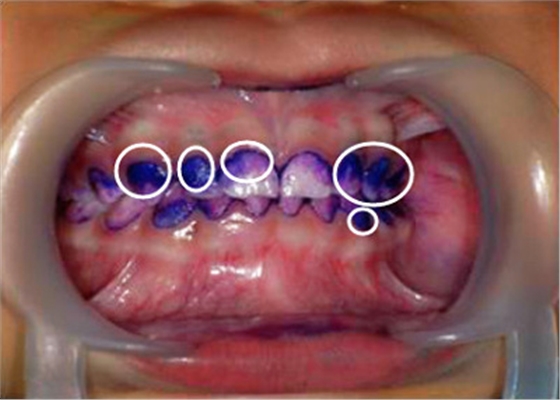

▲顏色較深的區(qū)域,就是牙菌斑堆積數(shù)較多的地方▼

② 牙菌斑染色,讓你更直觀了解口腔內(nèi)菌斑情況。

【圖中:紫色染色處為涂抹在牙齒上的菌斑顯示劑】

【圖中:顧客可直觀了解到自己口腔內(nèi)牙菌斑情況】

天天刷牙難道還會長很多牙菌斑?別不信,讓菌斑染色劑染色一下就知道了。直觀的提醒你,哪顆牙齒被你刷牙時疏忽了。